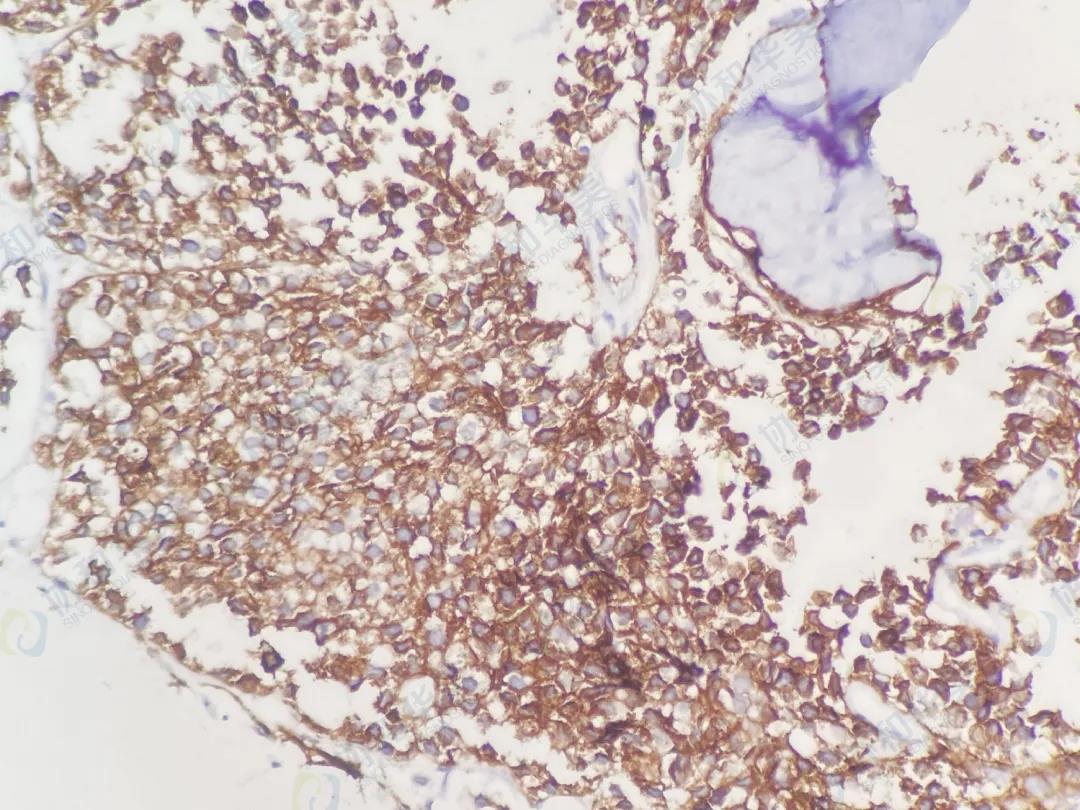

CD56                                                 Desmin